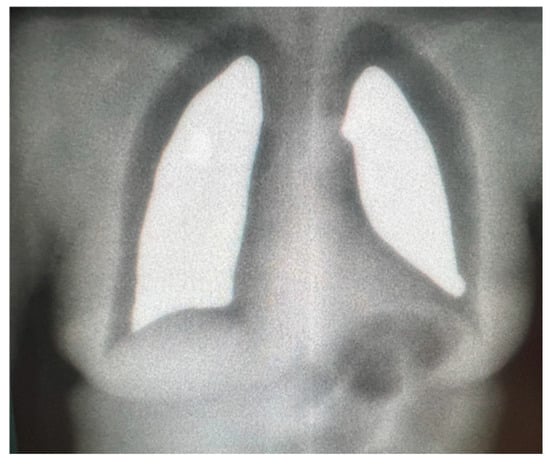

- Girinsky, T.; Socie, G.; Ammarguellat, H.; Cosset, J.M.; Briot, E.; Bridier, A.; Gluckman, E. Consequences of two different doses to the lungs during a single dose of total body irradiation: Results of a randomized study on 85 patients. Int. J. Radiat. Oncol. Biol. Phys. 1994, 30, 821–824. [Google Scholar] [CrossRef]

- Mekdash, H.; Shahine, B.; Jalbout, W.; Chehab, C.; Abdel Khalek, H.; Youssef, B. A simple technique for an accurate shielding of the lungs during total body irradiation. Tech. Innov. Patient Support Radiat. Oncol. 2017, 3–4, 13–18. [Google Scholar] [CrossRef]